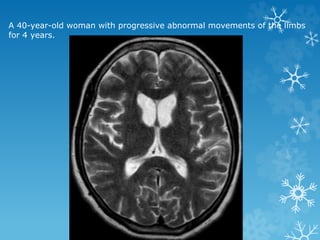

A 40-year-old woman with progressive abnormal movements of the limbs

for 4 years.

Band heterotopia